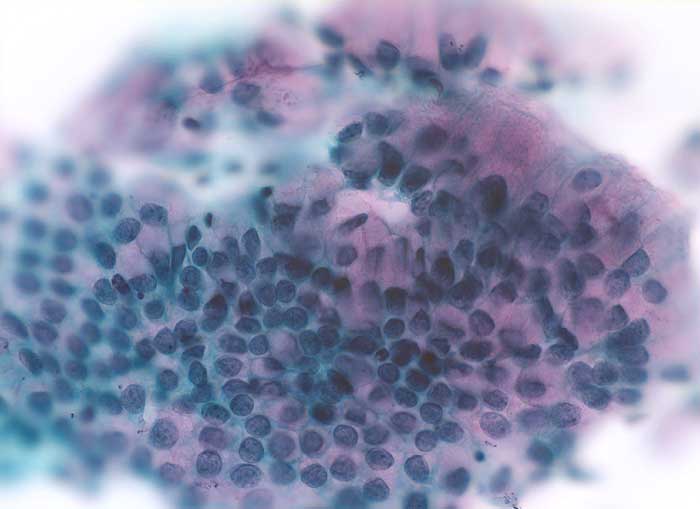

Zylinderepithelien

Normalbefund

Zervix

Zervixabstrich: regelmässiger honigwabenartiger Zellverband ohne Atypien. Die Zylinderzellen enthalten reichlich rosafarbenen Schleim.

Zytologie

400